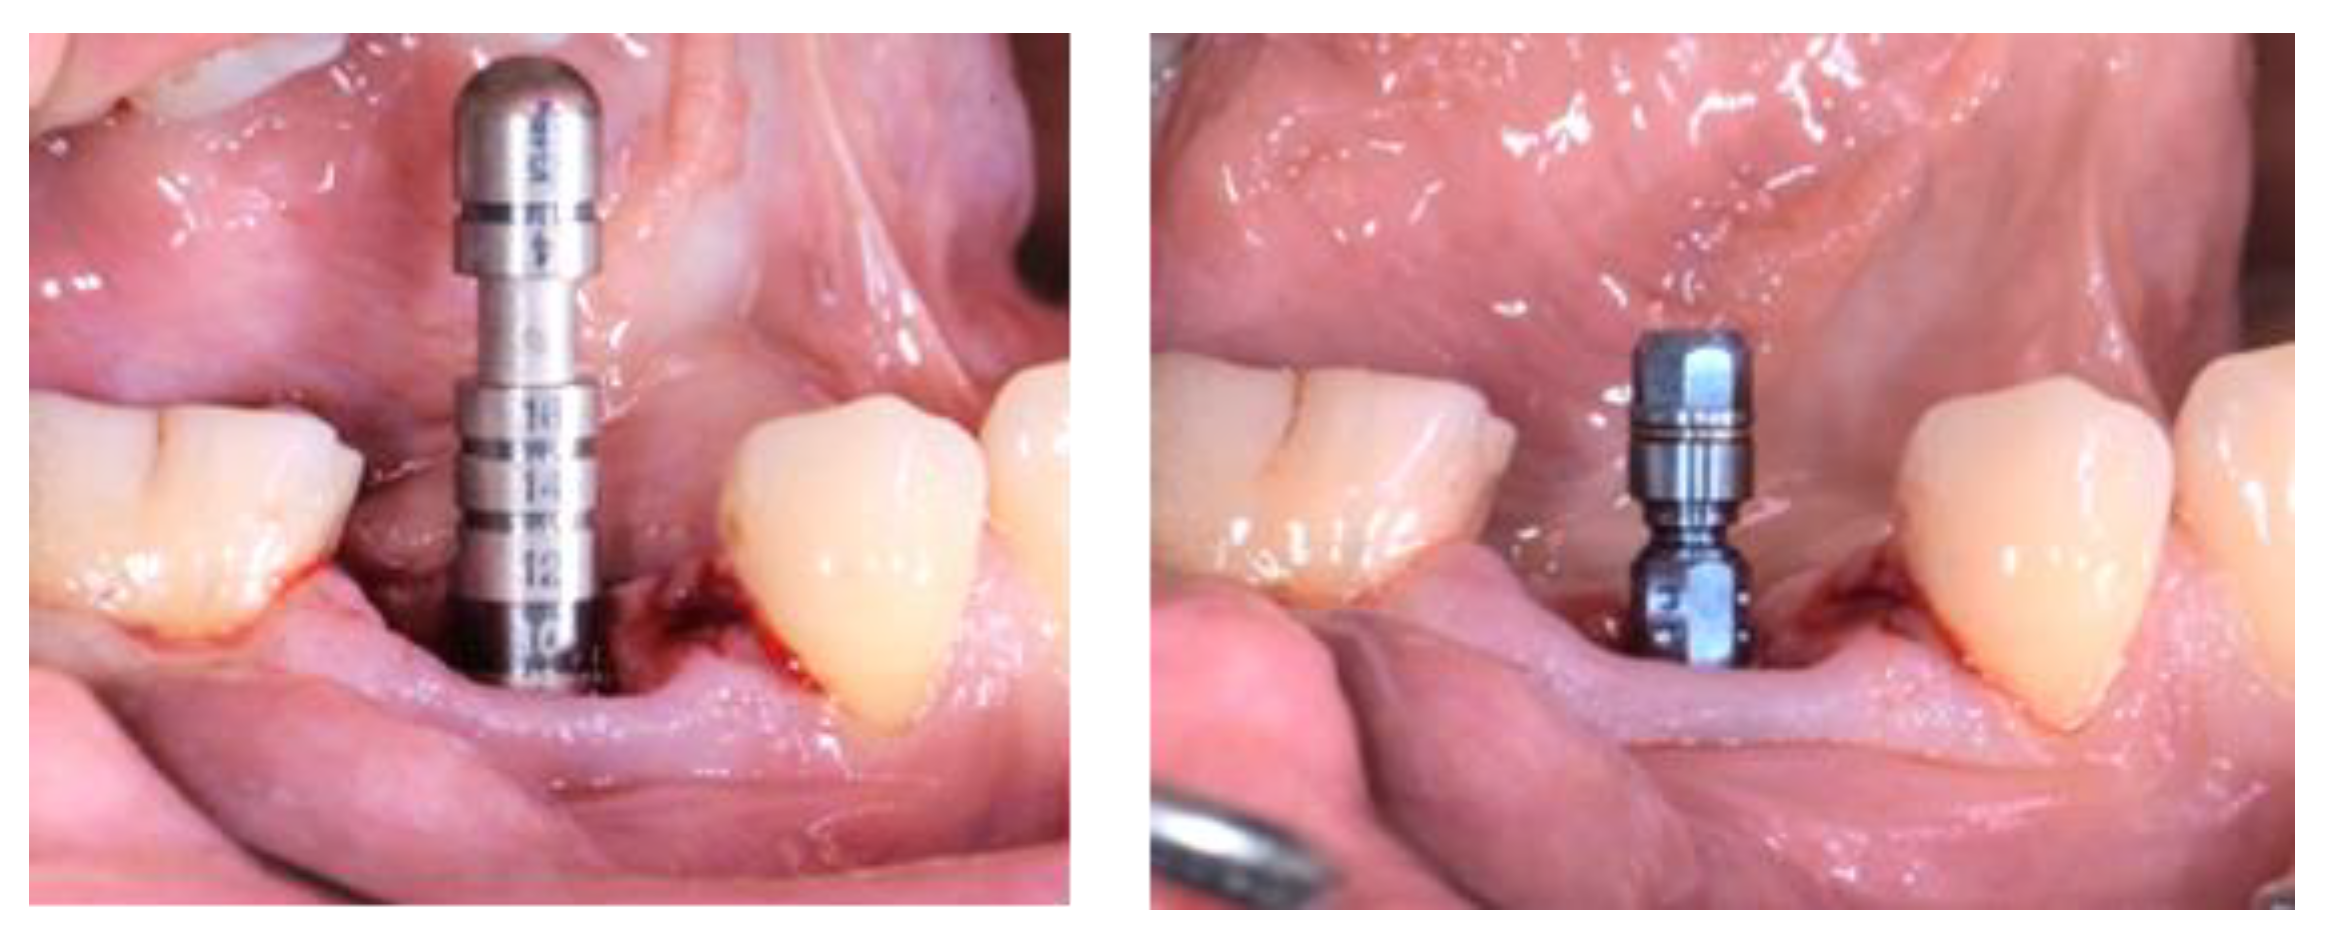

2.3. Treatment Procedure

2.5. Individual Cases Description

- Case 1:

- Case 2:

- Case 3:

- Case 4:

- Case 5: